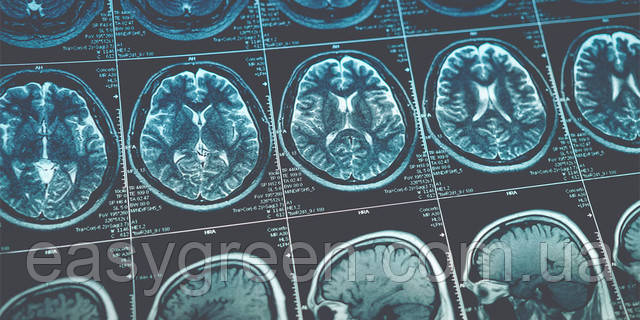

🧸 Відомо, що ожиріння причиняє проблеми з фізичним здоров’ям, але чи може воно також бути шкідливим для вашого розуму? Дослідження, опубліковане в журналі Cerebral Cortex, показує, що дитяче ожиріння пов’язане зі зменшенням сірої речовини в мозку.

📗 Для свого дослідження вчений і його колеги досліджували 258 дітей із ожирінням і 265 дітей із нормальною вагою. Вони проаналізували дані дослідження мозку та когнітивного розвитку підлітків Національного інституту здоров’я. Учасники брали участь у скануванні МРТ і виконали вимірювання виконавчих функцій як на початковому рівні, так і через два роки. Від усіх учасників було зібрано демографічну інформацію, а також було проведено порівняння між групою людей із ожирінням і нормальною вагою за віком, статтю, расою, освітою батьків і доходом домогосподарства.

⚠️ Дитяче ожиріння може бути фактором ризику багатьох проблем, таких як проблеми з диханням і травленням, депресія, низька самооцінка, соціальна ізоляція, труднощі у виконавчій діяльності тощо. Сканування мозку людей із ожирінням виявило структурні відмінності, такі як менша товщина та об’єм кори.